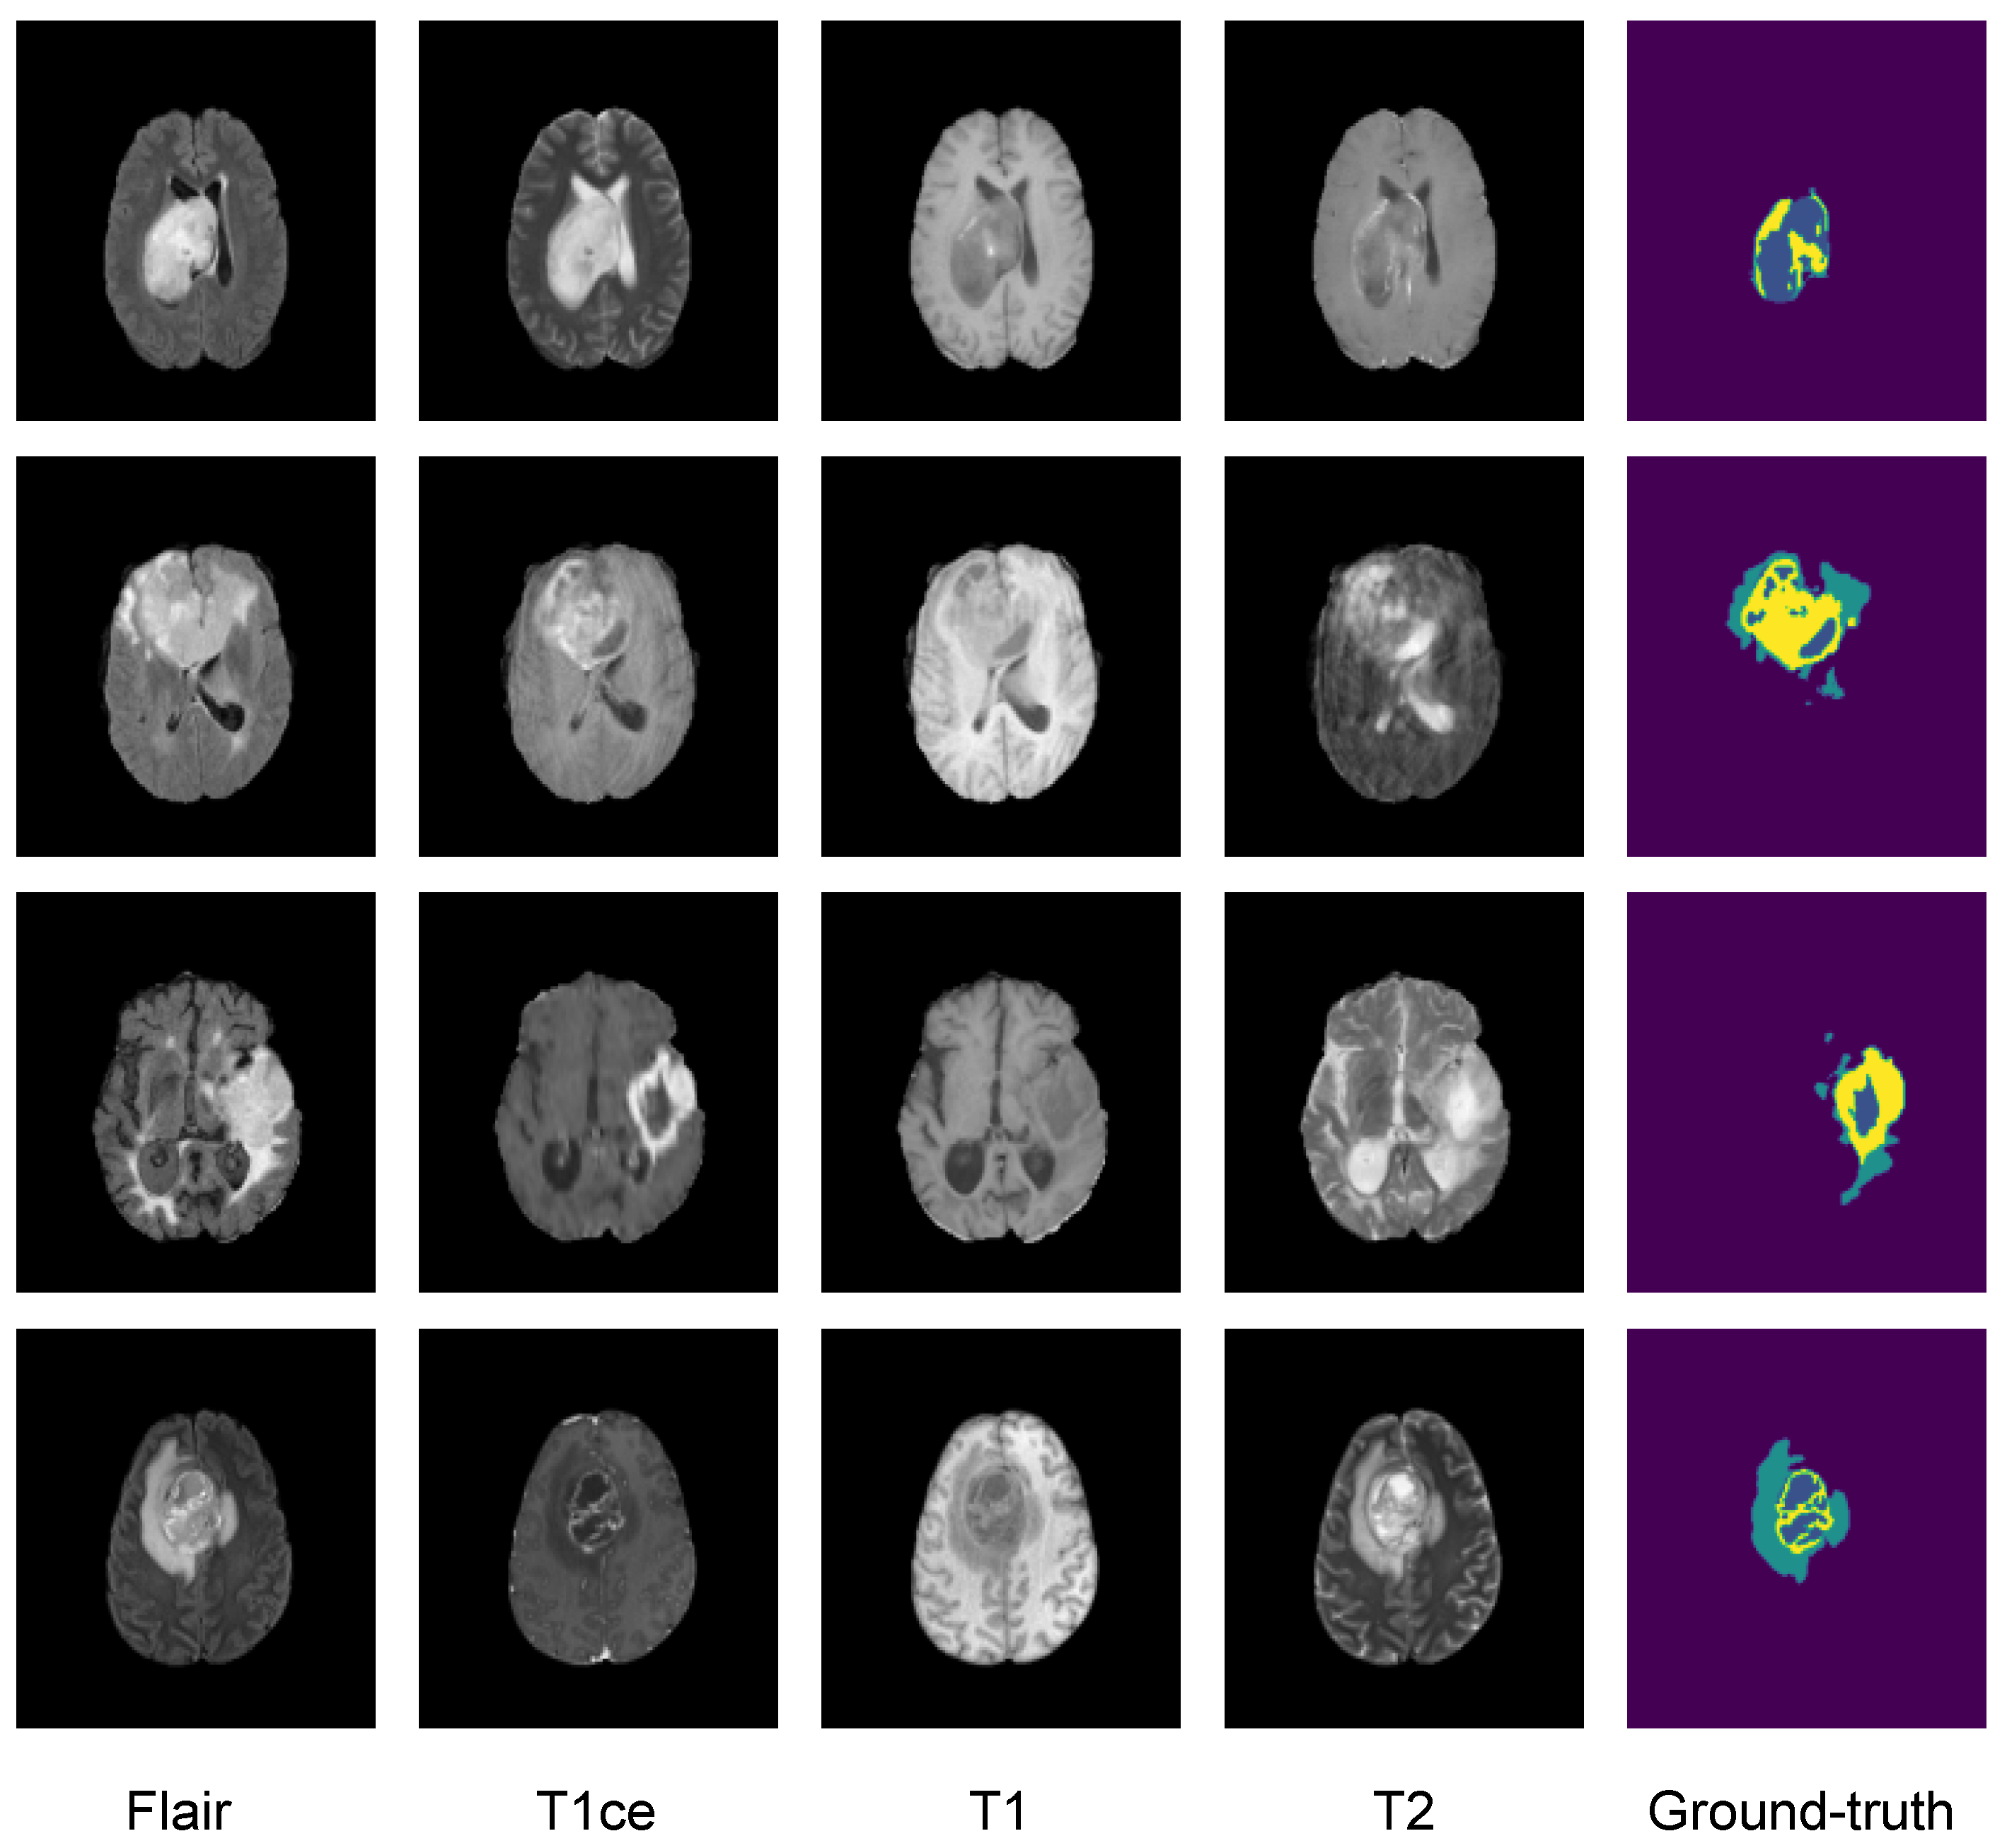

3.2. Dataset

3.3. Image Preprocessing